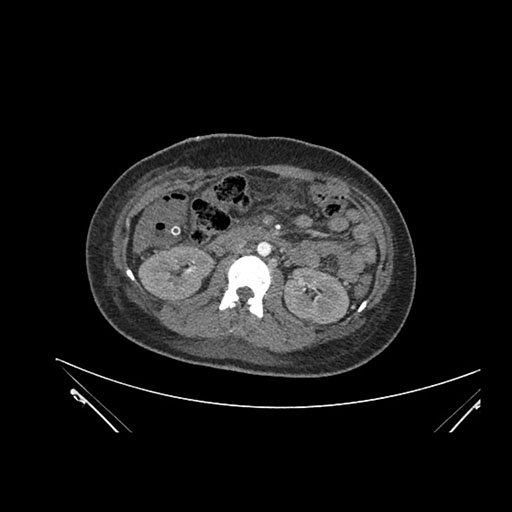

Imaging Analysis

Look through the patient's CT scan to identify any areas of concern for the necessary procedure.

Axial Arterial

Based on initial findings, which issue(s) would you be most concerned about?